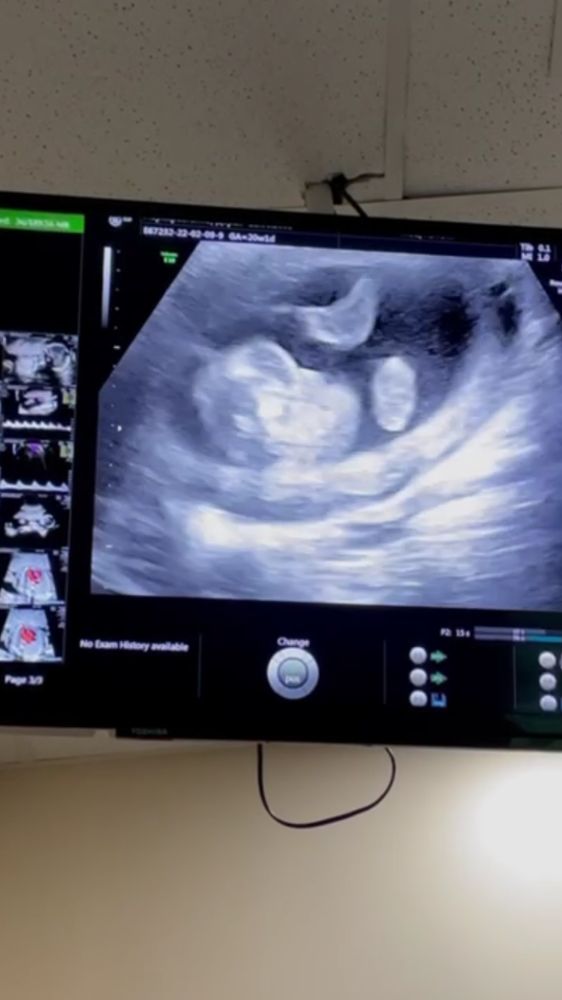

Мальчик или девочка?

Пол малыша